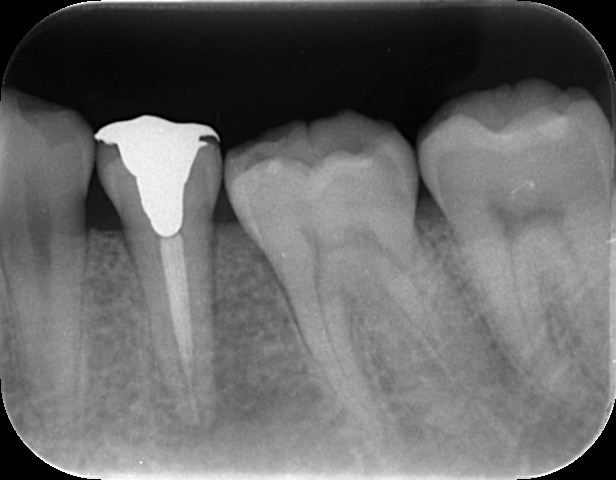

初診時所見: 打診痛(叩いた時の痛み)、根元の圧痛 頬側中央に10mmを超える垂直性歯周ポケットを認めました。

画像診断: レントゲンでは根の周囲に透過像(黒い影)を認め、CTでは根が割れて隙間が空いているようにも見える、非常にVRFの疑いが強い状態でした。